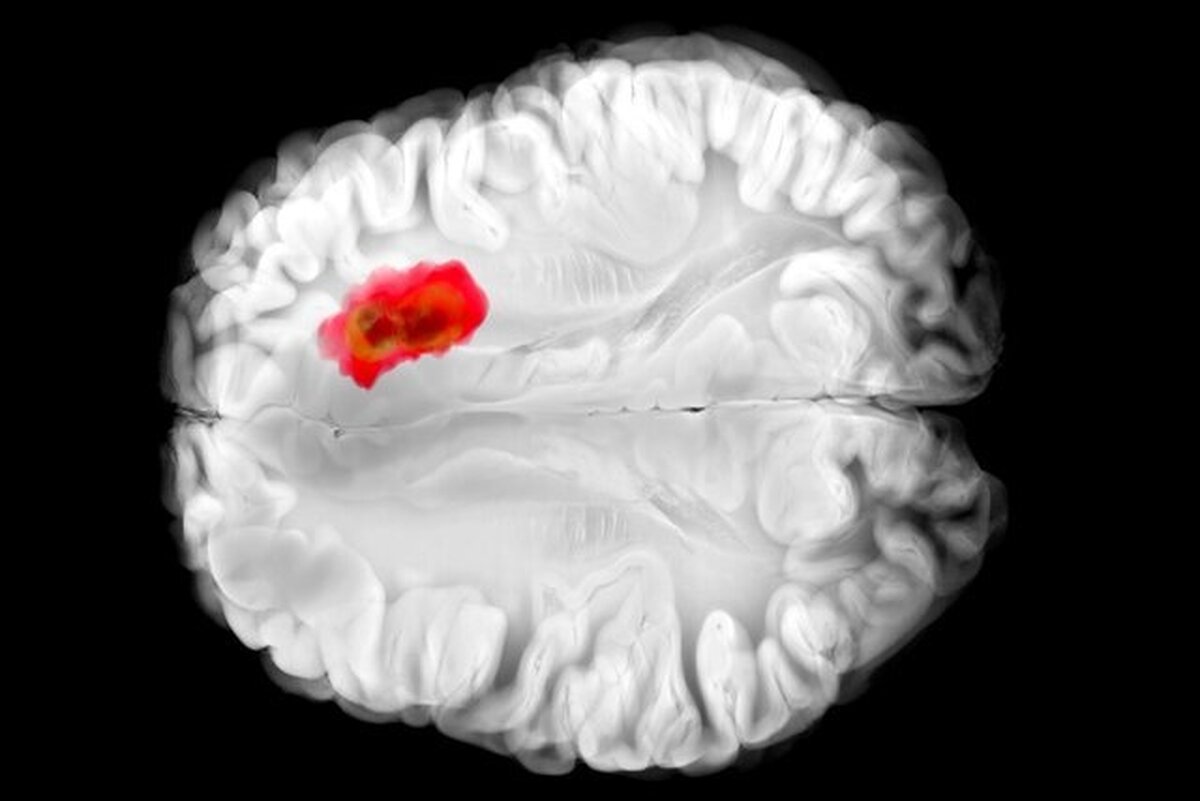

کشف دارویی برای مبارزه با کشنده‌ترین سرطان‌های مغز

به نظر می‌رسد یک دارو که پیش از این برای کنترل فشار خون بالا استفاده می‌شد، با یکی از کشنده‌ترین سرطان‌های مغز مبارزه می‌کند.

تصور می‌شود که همین آنزیم در سرطان‌های مغزی گلیوبلاستومای تهاجمی نقش دارد. این درک جدید از «هیدرالازین» می‌تواند راه را برای درمان‌های جدید سرطان هموار کند و همچنین اثربخشی دارو را برای اهداف فعلی آن بهبود بخشد.

مطالعات قبلی نشان داده‌اند که تومور‌های گلیوبلاستوما اغلب سرشار از ADO هستند و آن را برای تولید ماده شیمیایی به نام هیپوتائورین (hypotaurine) می‌ربایند که به سلول‌های سرطانی کمک می‌کند تا گسترش یابند، برای مدت طولانی‌تری زنده بمانند و فشار را تحمل کنند.

در آزمایش‌هایی که با سلول‌های گلیوبلاستومای انسانی انجام شد، «هیدرالازین» با مسدود کردن ADO رشد تومور را متوقف کرد.

البته این مطالعه هنوز در مراحل اولیه است. اثرات «هیدرالازین» هنوز باید در آزمایش‌های بالینی در افراد مبتلا به گلیوبلاستوما آزمایش شود، اما این یافته‌ها امیدوارکننده هستند و می‌توانند راهی برای کنترل شیوع این تومور‌های مغزی که به سختی درمان می‌شوند، باز کنند.